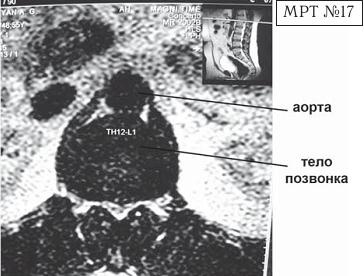

На МРТ № 18 наблюдаются грыжи межпозвонковых дисков в сегментах: — LIV-LV вентральной локализации с образованием каудального секвестра; при расположении межпозвонковой грыжи на один сегмент выше, «конфликт» с брюшной аортой был бы неизбежен; — LV-SI — дорсальная грыжа межпозвонкового диска, частично компенсированная спондилёзом МРТ № 19 ![]() МРТ № 20 ![]() На МРТ № 19 наблюдается дорсальная грыжа межпозвонкового диска шейного отдела позвоночника в сегменте СV-СVI с компрессией спинного мозга На МРТ № 20 наблюдается грыжа межпозвонкового диска шейного отдела позвоночника в сегменте CV—CVI и протрузия в сегменте CVI-CVII Замечу, что если грыжа межпозвонкового диска имеет достаточно большой размер и локализована в шейном отделе, то она способна вызвать не только соматические нарушения, но и даже психические расстройства. Причина кроется в сдавлении дурального мешка грыжей межпозвонкового диска (дуральный мешок — это герметичный соединительнотканный мешок, формируемый твёрдой мозговой оболочкой, в котором расположен спинной мозг). Как известно, спинной мозг не имеет болевых рецепторов. Однако вышеуказанная патология приводит к локальному устойчивому возбуждению определённых зон коры головного мозга. На субъективном уровне это может проявляться как постоянное чувство тревоги (так называемый «синдром ожидания»). Грыжи межпозвонковых дисков в грудном отделе позвоночника явление довольно редкое, но всё же наиболее опасное. Опасное потому, что эпидуральное пространство в грудном отделе позвоночника узкое по сравнению с другими отделами, в пределах всего 0,2–0,4 см по всей окружности дурального мешка (твёрдой оболочки спинного мозга). Поэтому даже небольшое грыжевое выпячивание может сдавить спинной мозг и вызвать тяжелейшие осложнения. Но, как уже говорилось, это явление в грудном отделе позвоночника редкое, поскольку высота межпозвонковых дисков довольно мала, всего около 3–5 мм, да и грудной отдел позвоночника менее подвижен по сравнению с другими отделами за счёт жёсткого рёберного каркаса, а значит, менее подвержен травматизации. МРТ № 21